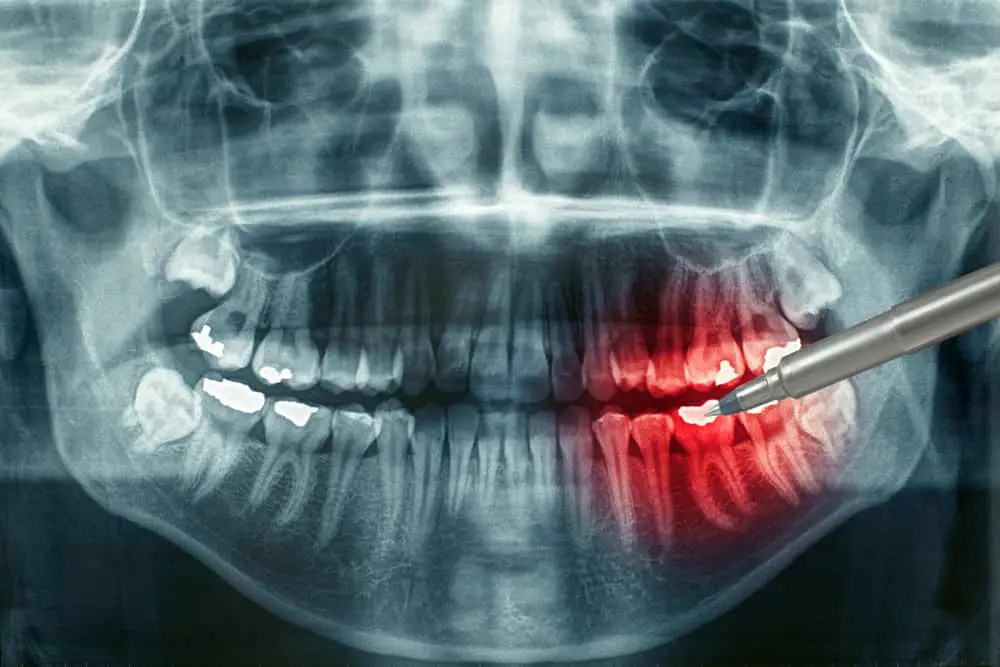

If you’re feeling low level, almost nagging pain in your teeth, gums, or jaw, you may feel like you can